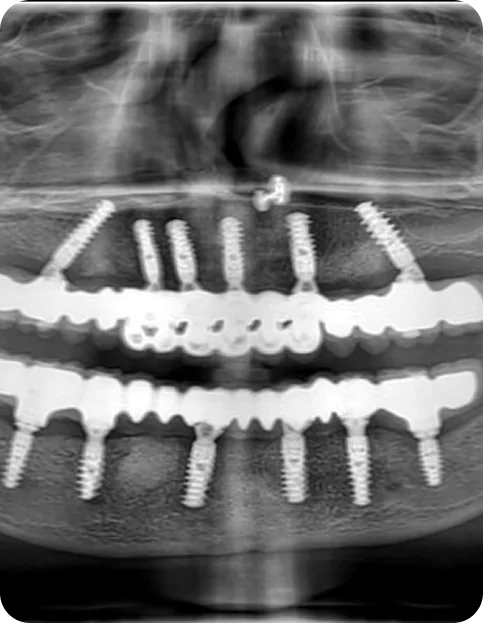

Full Mouth Dental Implants – Malo Titanium Bridge with Zirconia Crowns

Discover how full mouth dental implants using MALO titanium bridges and zirconia crowns can restore your smile with strength and aesthetic beauty.

Full Mouth Implants

Get a full arch restored using 4–6 implants for permanent teeth replacement.